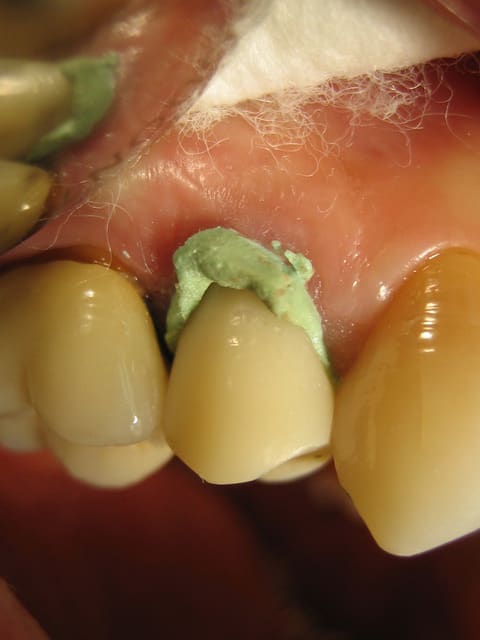

Capture d e cran 2015 02 19 10.59 - Eugenol